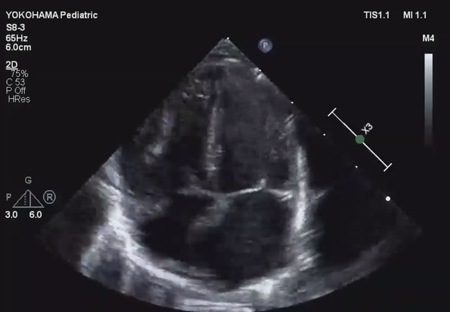

LV ejection fraction was down to 40% with moderate mitral regurgitation, whereas RV contractility was preserved. The biventricular volumes seemed well-balanced, and the LV end-diastolic diameter (15.9 mm) was within the normal range. Systolic RV pressure was estimated as 70 mmHg by regurgitation flow across the tricuspid valve (velocity 4.1 m/s), indicating persistent pulmonary hypertension. The ductus arteriosus had already closed. The foramen ovale (FO) was patent with very little blood flow through (Fig. 1A). The left atrium (LA) was dilated and non-contractile (Fig. 1B, Supplementary Video S1). Echocardiography showed a highly echogenic mass measuring 10×5 mm in the LA appendage, which was not mobile. The mass was suspected to be a thrombus (Fig. 1C, Supplementary Video S2). Blood tests indicated a high B-type natriuretic peptide (BNP) level (1,102.8 pg/mL) and a mildly elevated D-dimer level (2.27 µg/mL). There was no decrease in platelet count (279×103 /µL) or increase in clotting time (prothrombin time/international normalized ratio: 1.05, activated partial thromboplastin clotting time [APTT]: 29.9 s). The levels of fibrinogen (326 mg/dL), antithrombin-III (65%), protein C (35%), and protein S (68%) were within normal limits for neonates. There was no maternal history of systemic lupus erythematosus or antiphospholipid antibody syndrome, which could have affected neonatal formation of intracardiac thrombi.

Fig. 1 Echocardiographic findings

(A) Echocardiography at the time of admission (subcostal view) showed only a small slit-like blood flow across the foramen ovale. (B) Echocardiography on admission (four-chamber view) showed a dilated left atrium with an end-systolic volume of 4.0 mL. The left ventricular end-diastolic diameter was normal (15.9 mm). The left ventricular contraction was mildly reduced, with an ejection fraction of 40%. (C) Echocardiography on admission (short axis view) showed a highly echogenic and non-mobile mass (white *) of 10 mm ×5 mm in the left atrial appendage. (D) Echocardiography on day 9 showed improvement in left ventricular contractility. Atrial size had become normal, with a left atrial end-systolic volume of 2.1 mL. LA, left atrium; RA, right atrium.

We administered diuretics as well as continuous infusion of olprinone and unfractionated heparin. Continuous infusion of heparin was started at 10 U/kg/hr and gradually increased to 20 U/kg/hr, but the APTT was only slightly prolonged to 36.0 seconds on day 9. Daily echocardiography showed gradual improvement in LV function. Olprinone and diuretics were discontinued by day 9, because the LV ejection fraction improved to 65% and the LA size normalized (Fig. 1D, Supplementary Video S3). Marked mobility of the mass appeared in parallel with the restoration of LA contractility on day 10 (Supplementary Video S4). We performed a surgical thrombectomy on cardiopulmonary bypass so as to avoid systemic embolism. A white structure adhering to the LA appendage was excised (Fig. 2A), and pathological diagnosis was a calcified thrombus (Fig. 2B). The postoperative course was uneventful. Low-dose aspirin was started on the 3rd postoperative day. The patient was followed up on an outpatient basis, and aspirin was discontinued at 4 months postoperatively. At the time of this publication, the patient is 2 years old, and she has experienced no recurrent clots or embolic episode thus far.